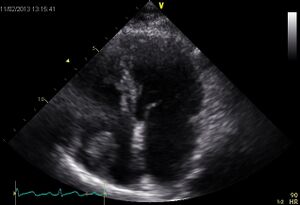

Examples1

Myxoma LA Thrombus RA